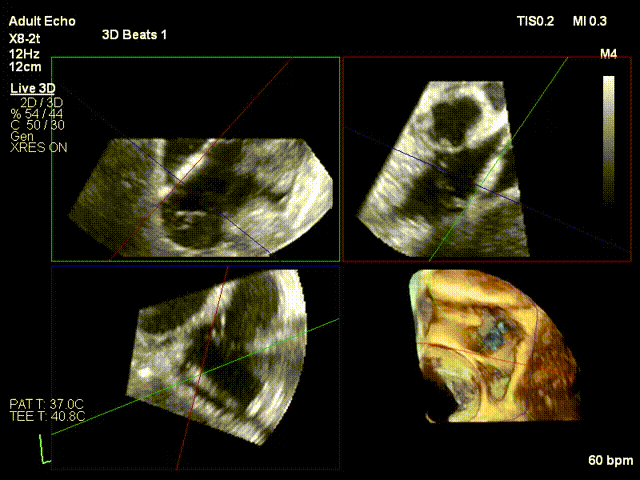

术前3D

术前3D彩色

二尖瓣交界联合彩色

前后瓣叶均可见栓系

反流主要来源于2区累及1、3区